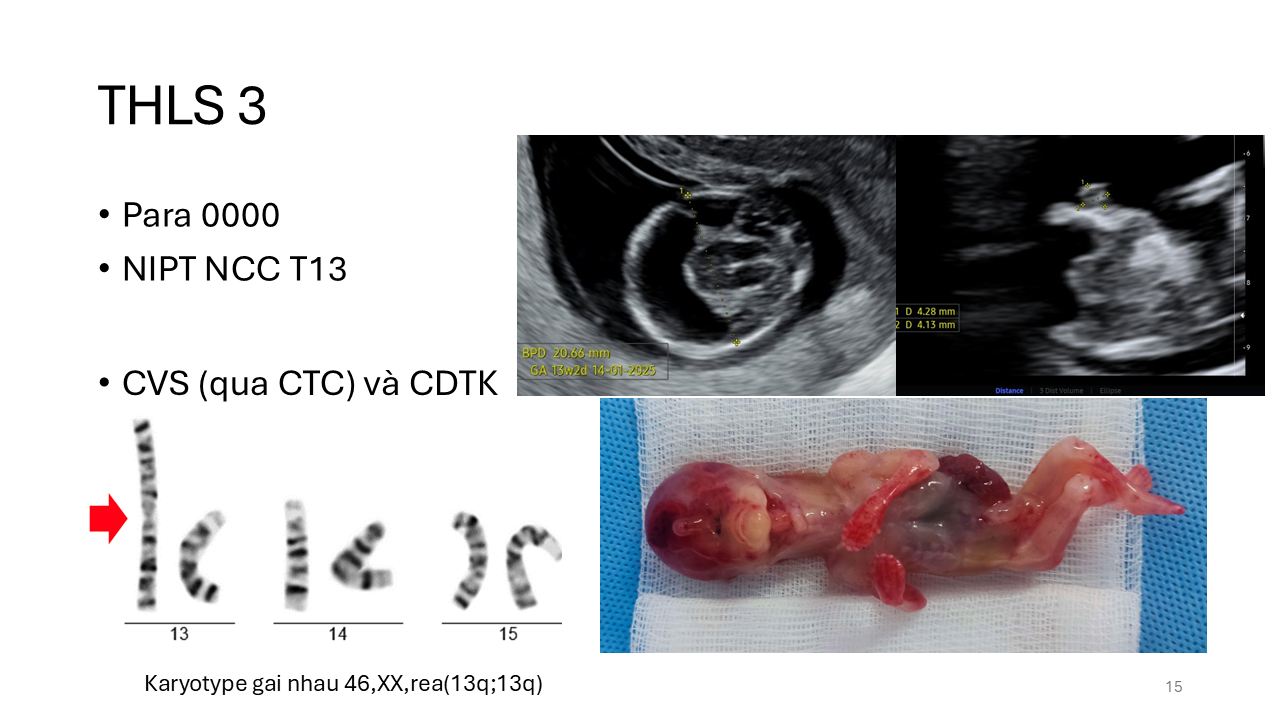

Cạm bẫy trong di truyền trước sinh: minh họa từ các trường hợp lâm sàng

TS. BS. Trần Nhật Thăng

Bệnh viện Đại học Y Dược TPHCM